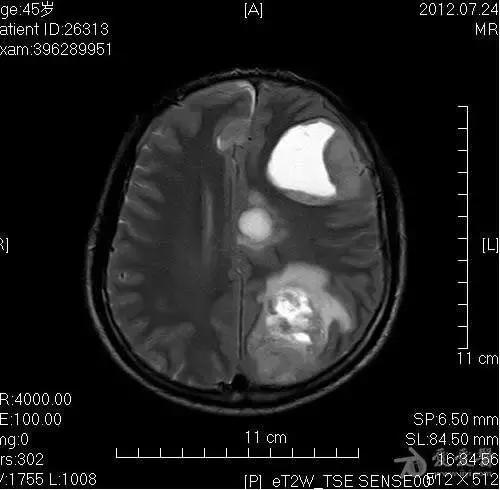

Fig 6 颅内占位

考虑占位性病变,建议某某检查

占位性病变是医学影像诊断学中的专用名词,通常出现在X射线、B超、CT等检查结果中。

是指被检查的部位有一个“多出来的东西”,这个“多出来的东西”可使周围组织受压、移位。

占位性病变通常泛指肿瘤(包括良性的、恶性的)、寄生虫等,仅仅是个现象而不涉及疾病的病因。

占位性病变绝不等于是癌症。

临床工作中,如果征象典型,可靠性80%-90%以上,一般报告肺癌可能性大、肝癌可能性大等。若可靠性在60%-70%,表述为:考虑占位性病变,医生会要求患者提供更详细的病史,以及参考其他检查,进一步明确诊断。各系统占位性病变最终诊断依赖于病理检查(穿刺取样或直接切下来放在显微镜下观察)。